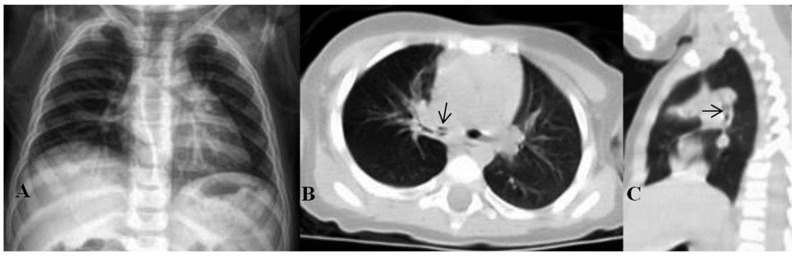

Abstract Image